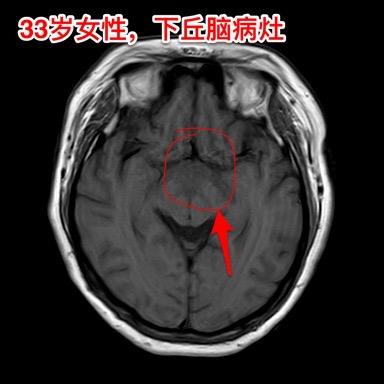

年轻女子四年体重从120斤增到220斤。河北石家庄地区33岁女性,四年前(29岁)开始出现问题,内分泌紊乱(生理周期停了)、多饮多尿,贪食,总爱吃东西,体重稳步增长,四年时间从120斤增长到220斤! 而且还出现多睡,一天到晚躺下就想睡觉。近期还出现记忆力差、头脑糊涂。自从四年前发病后就不能工作了。 2024年12月15日外院的磁共振检查发现下丘脑病变,怀疑是颅咽管瘤。 患者的弟弟找到我,希望我能为他的姐姐解除病痛。 经过仔细分析病人的影像学资